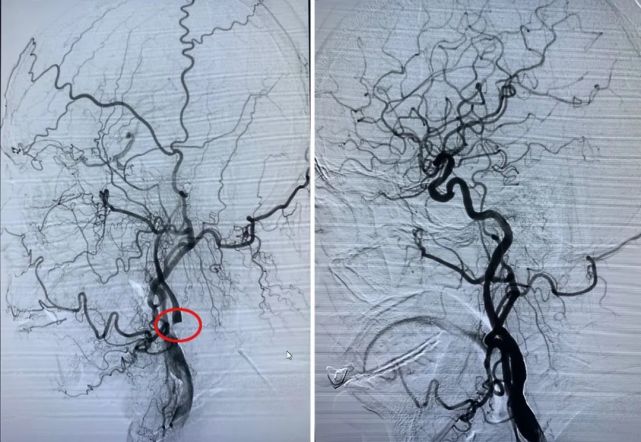

图左圈圈处为颈动脉狭窄处,图右为术后血管开通